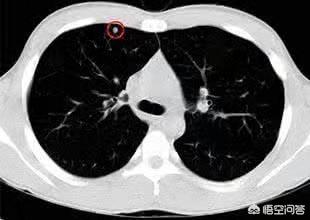

肺結節の定義について、中国医学ガイドラインは次のように述べている:画像診断(胸部CT)により、直径3cm以下の限局性、円形状、密度増加した固形または亜固形の肺影が認められ、孤立性または多発性の可能性があり、肺無気肺、肺門リンパ節腫大、胸水を伴わない。

一般に、肺にできる直径3cm以下の密度増加影を肺結節と呼びますが、その危険度は大きさだけでなく、結節の形態、密度、増殖速度も合わせて判断する必要があります。

一般に、直径8mm以上の結節は細心の注意が必要であり、特に、形が不規則であったり、あるいはバリ状のパターンを伴っていたり、実像と虚像が混在していたり、胸膜に隣接していたり、胸膜陥凹が出現していたりする場合は、悪性腫瘍の可能性を強く警戒する必要がある。必要に応じて穿刺生検や直接切除を行う。

第一に、肺結節の区分については、現在、8mm以上3cm以下の肺結節を典型的な肺結節と呼び、8mm未満の肺結節のみを小結節と呼んでいる!

第二に、肺結節の大きさと良性・悪性のリスクの程度には相関関係がある!一般的に、5mm未満の肺結節が悪性である確率は0~1%、5~10mmが悪性である確率は6~28%、20mm以上が悪性である確率はかなり高く、ほぼ60%以上と考えられており、これはすりガラス状の肺結節の悪性の程度と同様である!

1.直径1.5cm以上または8~15mmの固形結節で、悪性腫瘍の徴候があるもの;

2.直径8mmを超える亜固形肺結節(混在性粉砕結節)。

例えば、左下肺に2.2cmの混合膜ガラス結節があるこの中年女性は、リスクの高い結節であり、実際、肺腺癌の典型的な徴候を有している。血管の進入と肥厚を伴う明瞭な地硝子影、気管支気腹徴候、遠位胸膜浸潤、浸潤性肺腺癌の外科的病理所見このような病変は経過観察には勧められないので、転移や治療の遅れを避けるために、さらに詳しく調べてはっきりさせる必要がある。